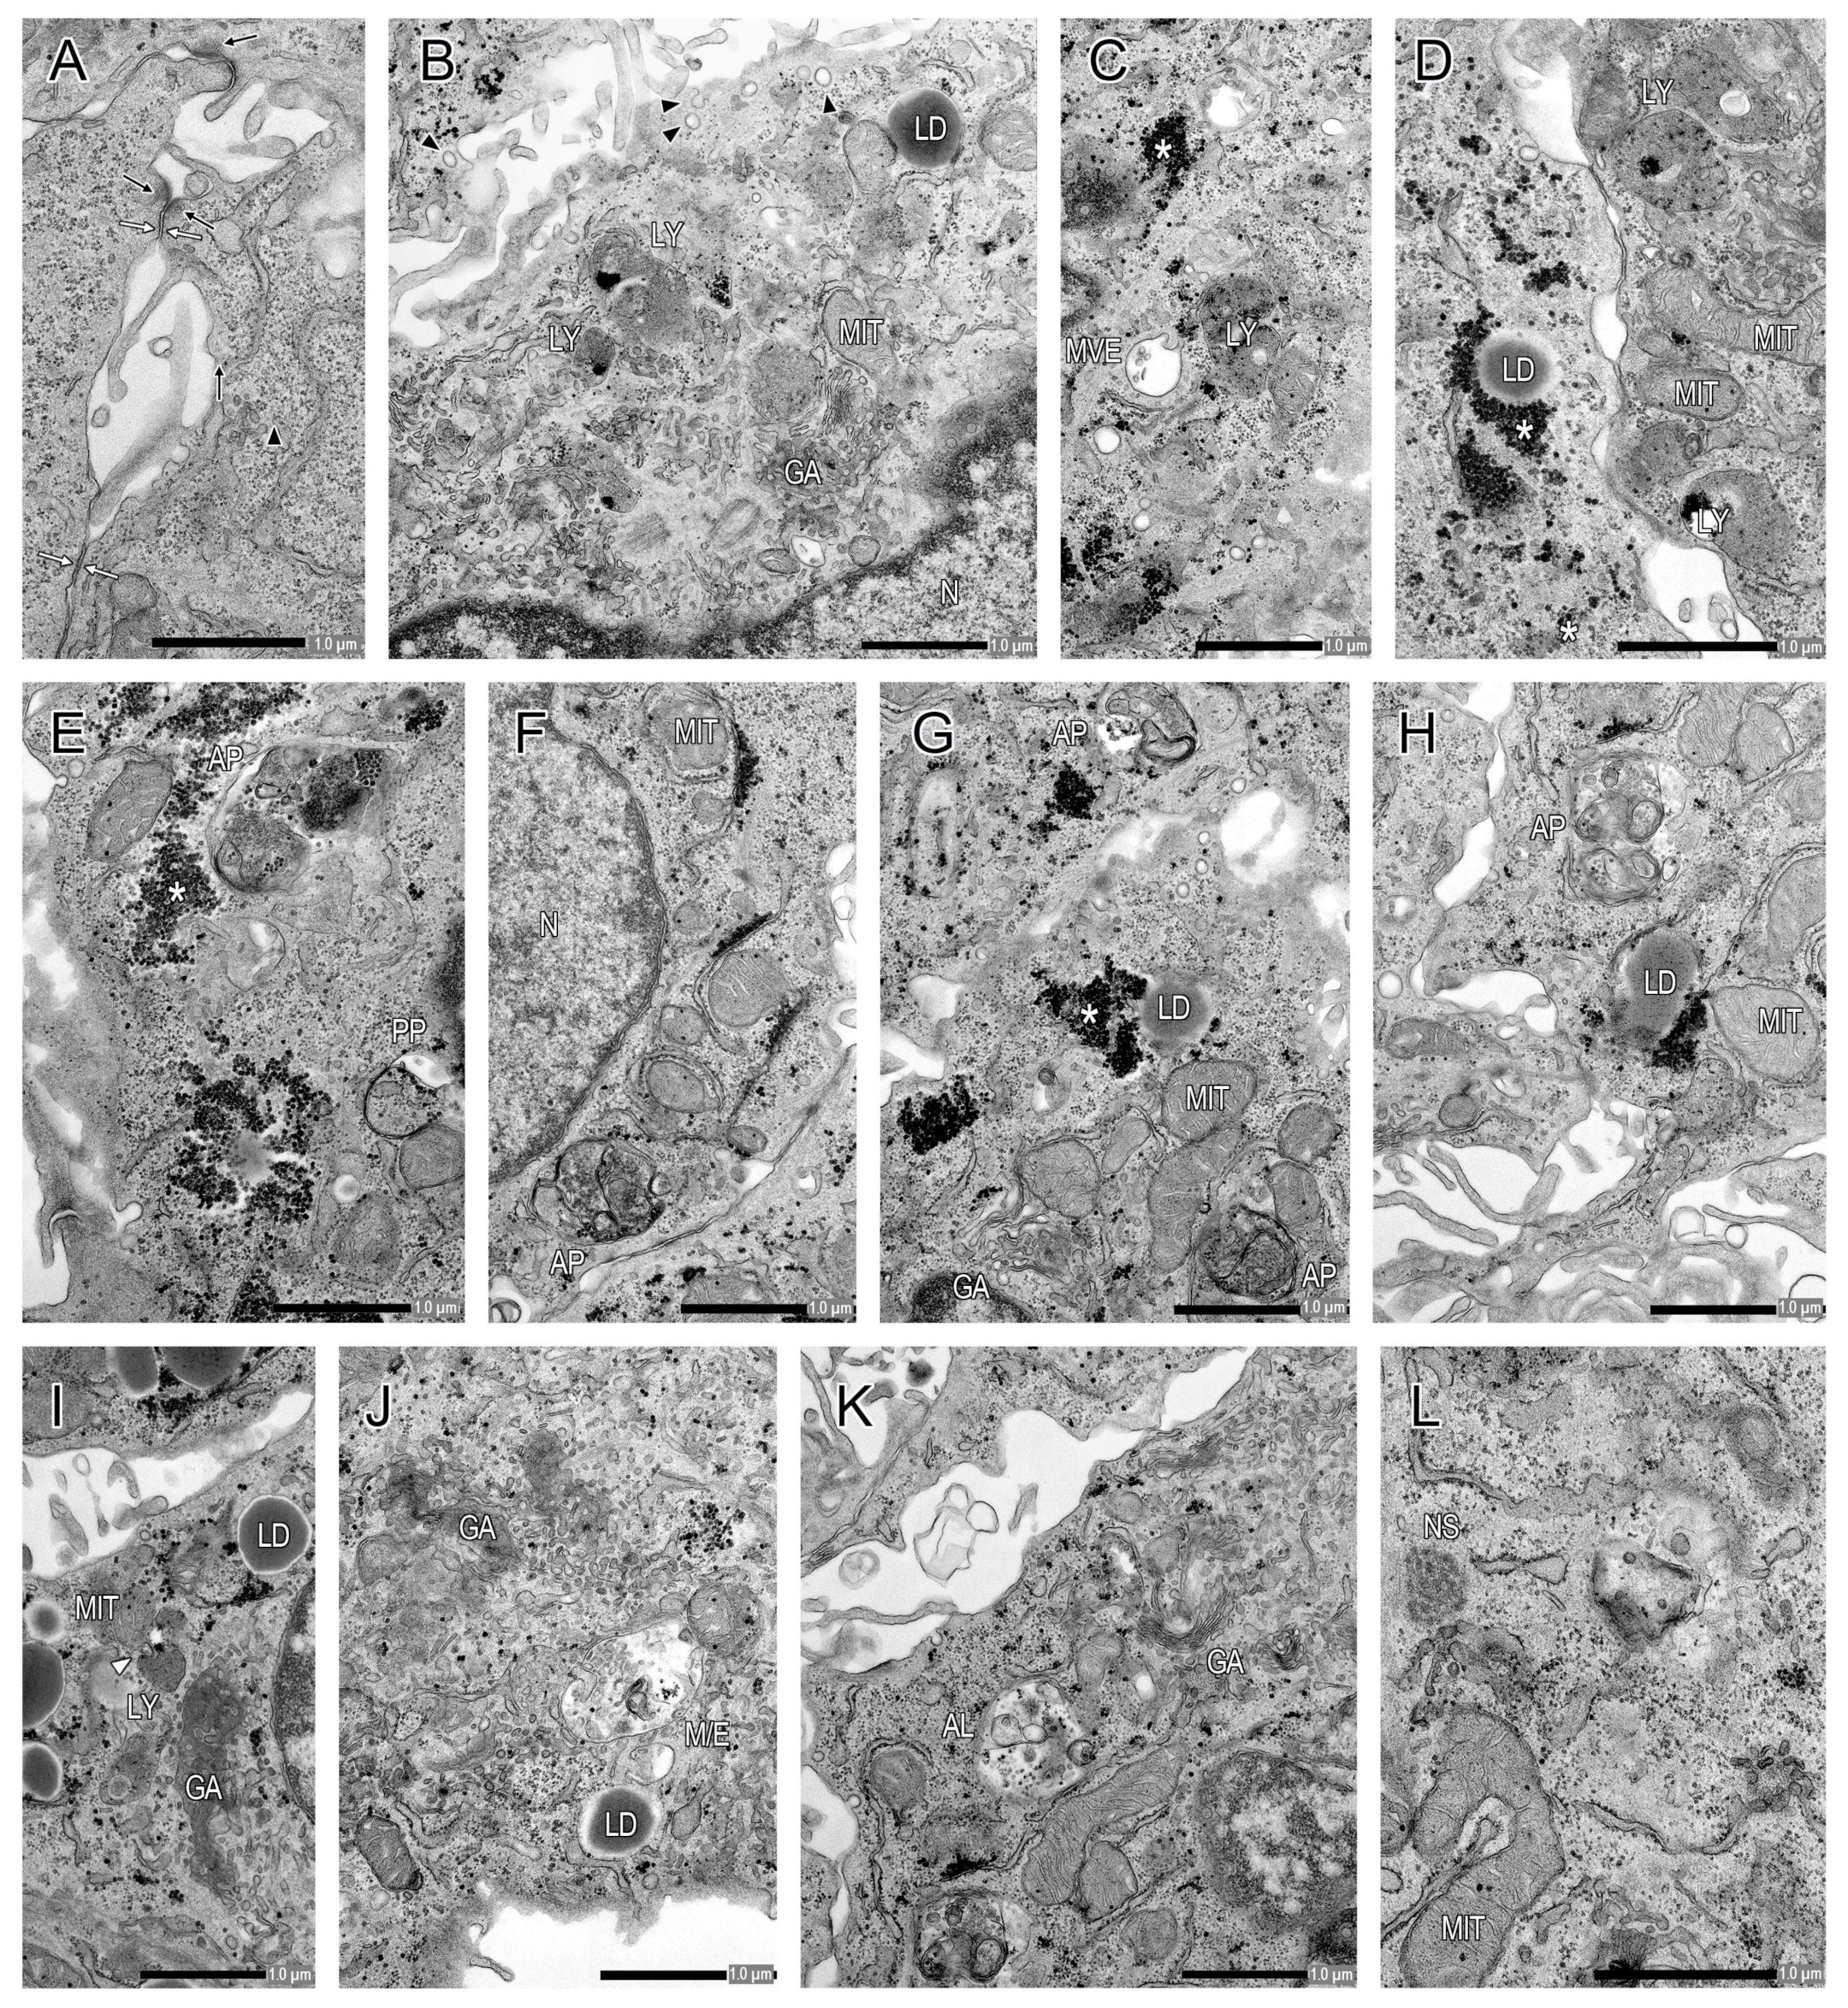

2.2. Transmission Electron Microscopy Analysis of Cultured Primary CTB Cells